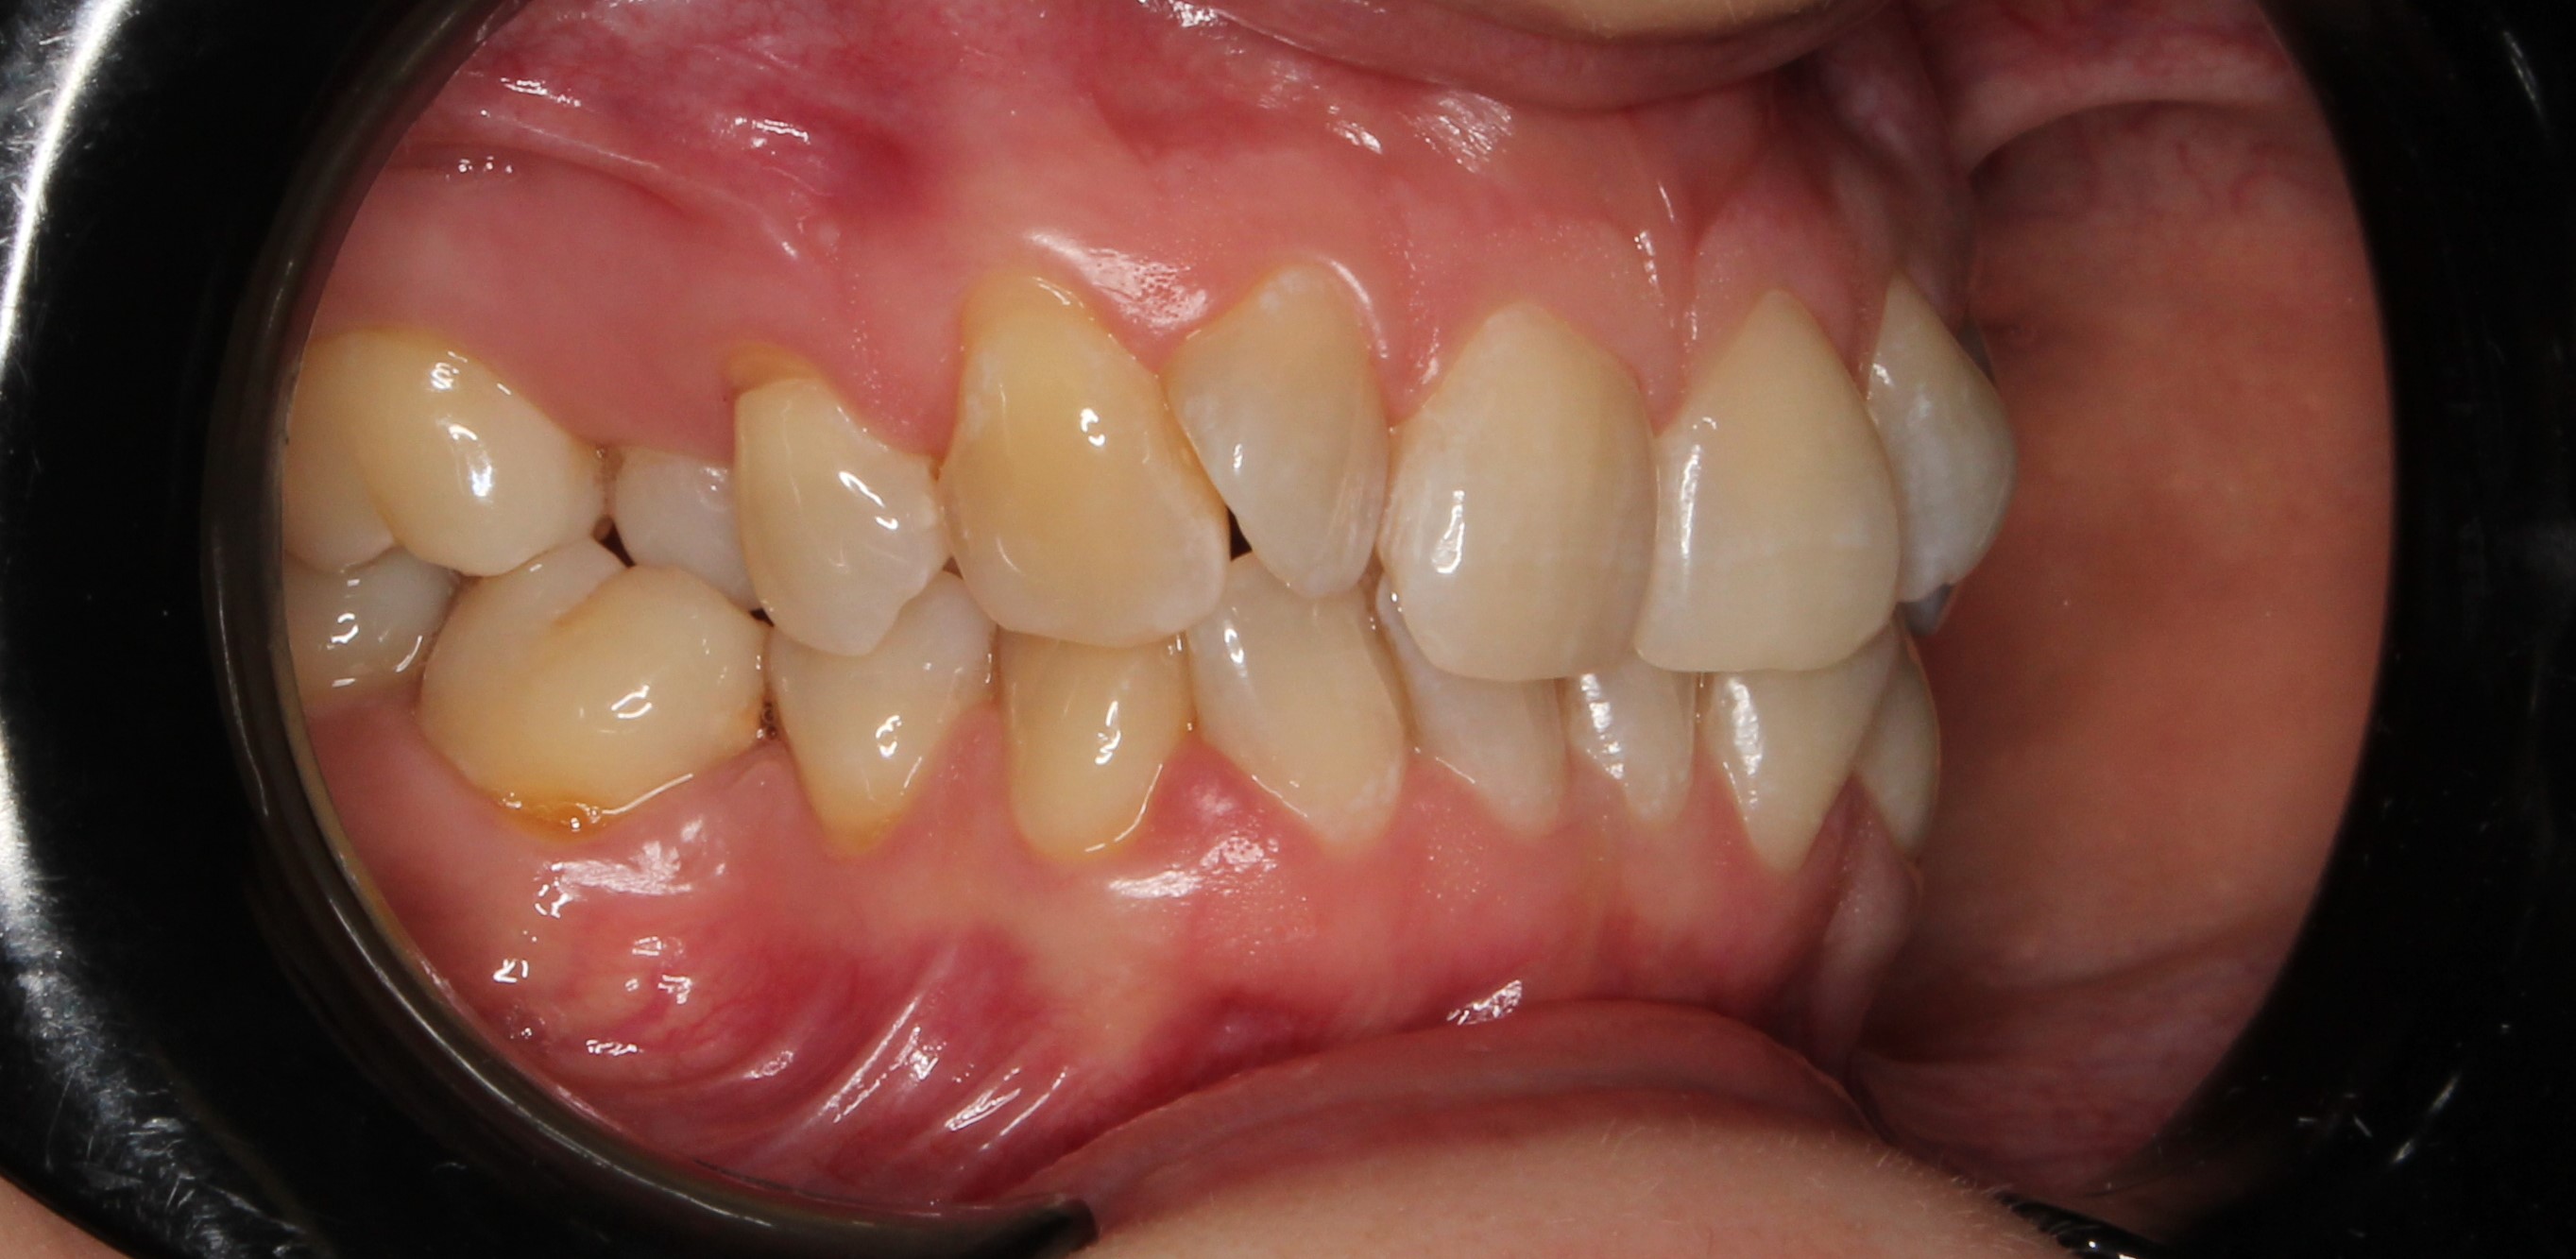

До и После: Фиксация элайнеров Eurokappa на зубы

Начало лечения на элайнерах Eurokappa. Фиксация аттачментов и установка незаметных капп для выравнивания зубов.